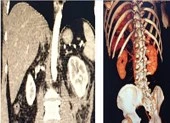

Ca phẫu thuật diễn ra trong 8 giờ với 2 kíp thực hiện song song: Một kíp thực hiện phẫu thuật lấy toàn bộ đơn vị tổ chức vùng da lưng to có mạch máu nuôi để chuyển đến vùng cần tạo hình. Sau đó nối động mạch, tĩnh mạch, dây thần kinh để đảm bảo tổ chức vi phẫu được cấp máu nuối tốt, phục hồi tổn thương cho bệnh nhân.Một kíp phẫu thuật khác lấy da đầu của bệnh nhân để thực ghép da diện rộng cho mu bàn chân.

Sau một thời gian điều trị, chăm sóc tích cực, vạt vi phẫu đã hoàn toàn ổn định, che phủ toàn bộ phần lộ xương mặt gan chân, bệnh nhân không còn tình trạng nhiễm trùng. Phần da mặt mu chân của bệnh nhân đã sống tốt, bám tốt vào nền nhận. Các bác sĩ bệnh viện E hy vọng sau khi tập phục hồi chức năng, chân bên phải sẽ liền phần gan bàn chân và gót, bệnh nhân có thể đi lại được.